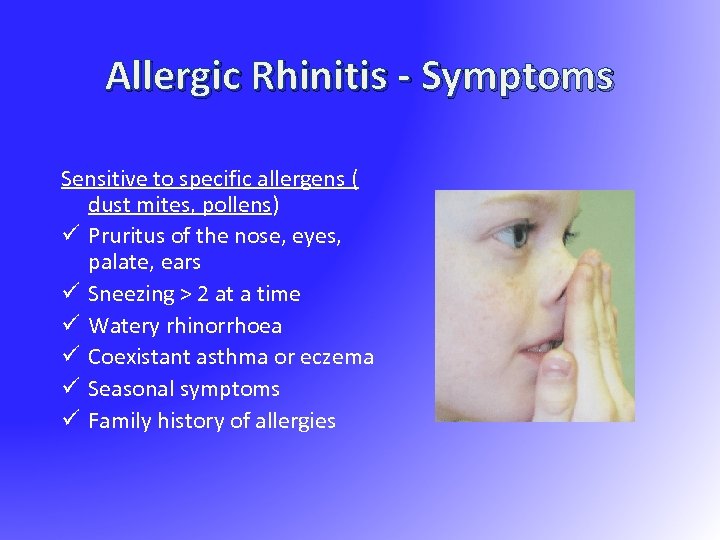

Allergic Rhinitis - Symptoms Sensitive to specific allergens ( dust mites, pollens) ü Pruritus of the nose, eyes, palate, ears ü Sneezing > 2 at a time ü Watery rhinorrhoea ü Coexistant asthma or eczema ü Seasonal symptoms ü Family history of allergies

Allergic Rhinitis - Symptoms Sensitive to specific allergens ( dust mites, pollens) ü Pruritus of the nose, eyes, palate, ears ü Sneezing > 2 at a time ü Watery rhinorrhoea ü Coexistant asthma or eczema ü Seasonal symptoms ü Family history of allergies